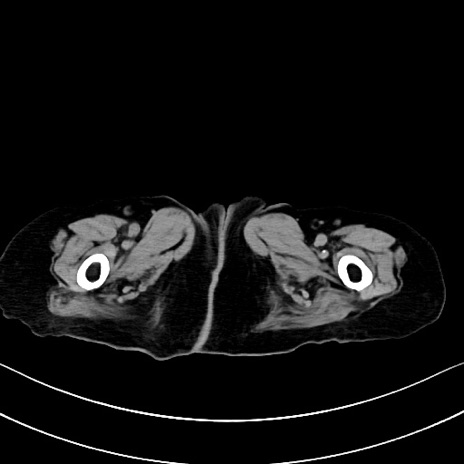

横断像